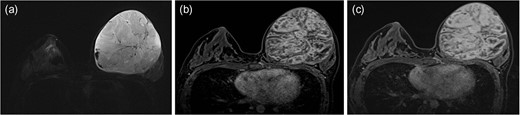

Axial STIR image of breast MRI shows a well-circumscribed mass with heterogeneous signal intensities (SIs), consisting of solid components with iso-to-high SIs, with interspersed by areas of cystic portions. These cystic areas are also noted along the periphery of the mass. Dark focal SI due to hemorrhage and signal voids due to fast flowing blood vessels are seen (a). On dynamic contrast-enhanced T1WI, the solid portions shows early intense heterogeneous enhancement on 1 min image (b) with a persistent pattern on the late phase of 5 min image after contrast administration (c).